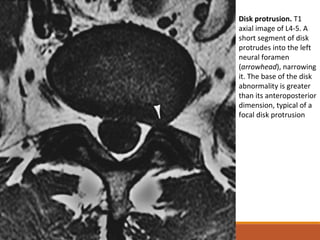

Disk protrusion. T1

axial image of L4-5. A

short segment of disk

protrudes into the left

neural foramen

(arrowhead), narrowing

it. The base of the disk

abnormality is greater

than its anteroposterior

dimension, typical of a

focal disk protrusion